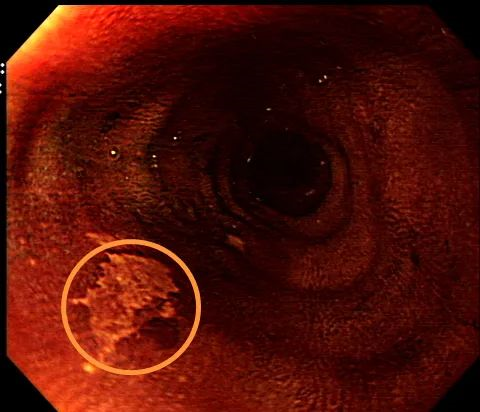

食管染色后观察并取病检

“精准的技术,加上胆大心细,是能诊断出这次早癌的关键,同时也为患者争取到宝贵的治疗时间。”内镜中心负责人陈主任说道,此例患者是因为胃部疾病行胃镜检查发现食管早癌,也是不幸中的万幸。